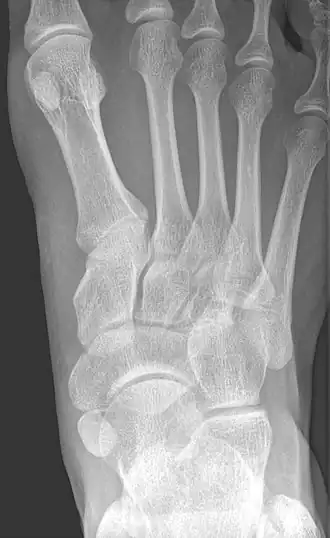

Radiological images

-

From left to right: Type 1, 2 and 3 -